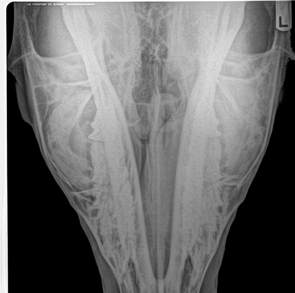

x-ray of Penny’s nose.

Penny is a 20ish yr old QH mare, kid gentle, great feet. She has a growth in her sinus that needs to be removed to save her, prognosis is very good with surgery. 3 vets are currently working with her and have donated a portion of their services to help this very nice mare. Penny had surgery on 8/31/11 and a tennis ball sized tumor was removed from her sinus cavity. Donations are appreciated. Penny’s foster home has offered her the lifetime home this nice mare deserves